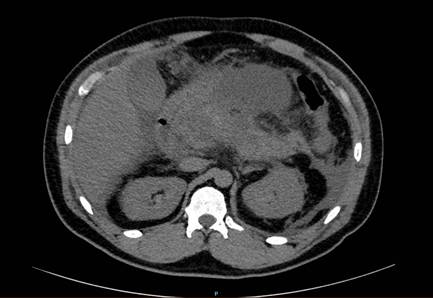

En busca de etiología, se realizó una ecografía de hígado y vías biliares donde no se evidenciaron cálculos ni dilatación de la vía biliar; se solicitó calcio sérico de 7.8 mg/dL y triglicéridos de 320 mg/d. Por incremento del dolor dos días posteriores al inicio del tratamiento, se ordenó una tomografía contrastada de abdomen y pelvis, cuyo resultado mostró necrosis pancreática del 50%, asociado a colección peripancreática de 83 mm de diámetro compatible con Balthazar D (Figura 1). Por este hallazgo se traslada al paciente a la Unidad de Cuidados especiales, donde se realiza drenaje de colecciones peripancreáticas.